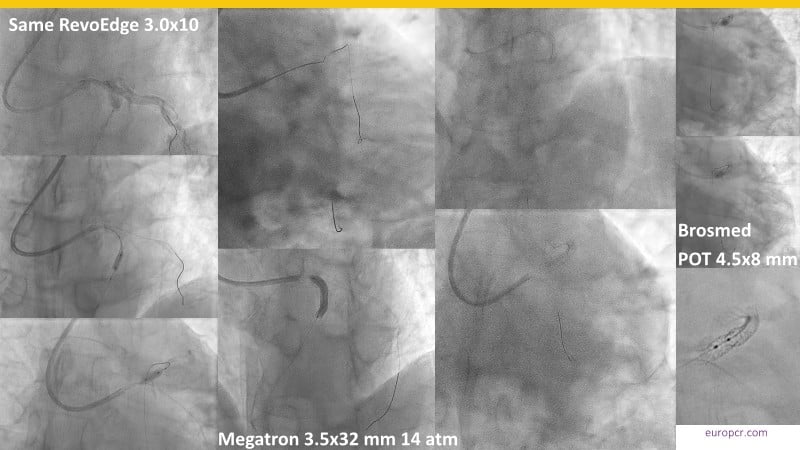

Discover how the next-generation RevoEdge high-pressure cutting balloon is transforming PCI with innovative design and proven clinical outcomes. This session presents a multicenter randomised trial and real-world case discussions, showcasing RevoEdge’s effectiveness in tackling resistant, complex lesions—including long, tortuous, and fibrotic cases. Learn practical tips, tricks, and intravascular imaging insights to optimize lesion preparation and improve patient outcomes. Don’t miss this opportunity to see how RevoEdge helps you cut through challenges and conquer PCI complexities.

- To explore the innovative design of RevoEdge: the next-generation high pressure cutting balloon

- To learn about the clinical benefits and tips and tricks of using RevoEdge high pressure cutting balloon in different types of complex lesions through case-based discussion